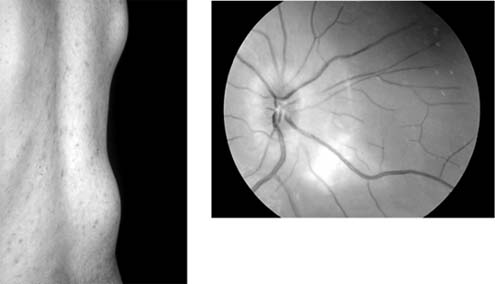

Iritis and iridocyclitis occur in the secondary stage of syphilis along with the rash in about 5% of cases. The inflammation may involve the posterior segment, including the pigment epithelium and the retinal capillaries (Figure 15-28).

Figure 15-28

Figure 15-28: Secondary syphilis. Bilateral visual loss occurred in a 24-year-old man. Late fluorescein photographs showed disk leakage with dilation and leakage of peripapillary capillaries.